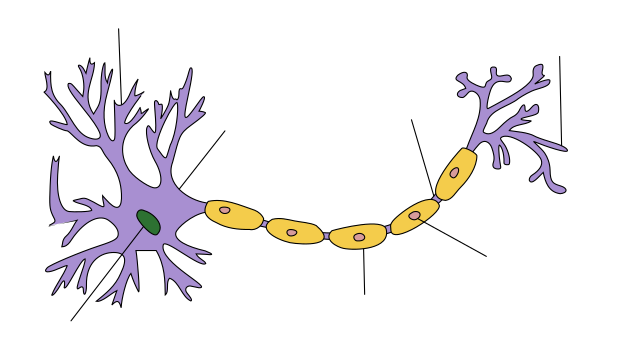

Quellen/Ursprung bioelektrischer Signale: Nerven und Muskeln

|

|

|---|

Beide Gewebearten haben spezielle Eigenschaften:

- Erregbarkeit

- elektrisch

- mechanisch

- chemisch

- Erregungsfortleitung:

- innerhalb der Zelle vom erregten Abschnitt zum benachbarten Abschnitt

- von Zelle zu Zelle